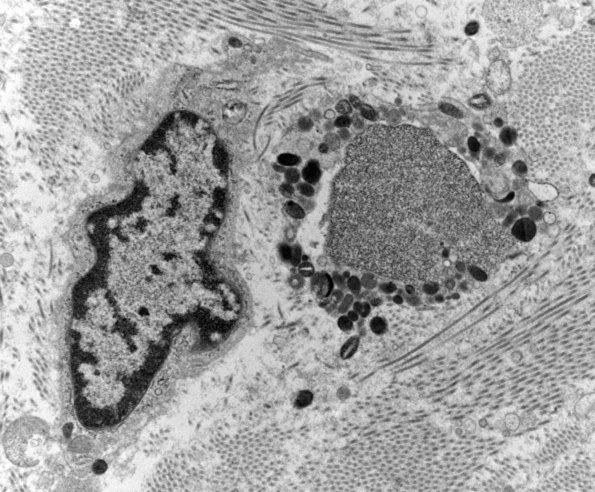

Washington University Experience | PERIPHERAL NEUROPATHY | 19 TRAUMATIC INJURIES | 12E3 (Case 12) C5 N root_008a - Copy

Within collagenous areas swollen structures were encountered which consist of autophagic vacuoles and tubulovesicular elements. We think these are swollen regenerative structures similar to axonal growth cones, likely by deviation into an area not conducive to regeneration. (electron micrographs)